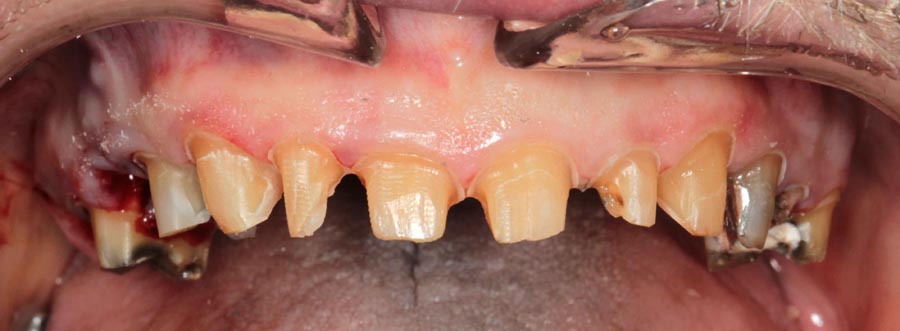

Patient wanted to see what longer, prettier teeth would look like. Crown preparations to prepare for crown lengthening and temporary crowns/bridge.

The patient returns six months later without his temporary bridge. His grinding caused their destruction. He was saving money for implants. He decided that he would rather have full mouth implants because he believed that his tooth would eventually fail if he saved them now. And he believed he could only afford this treatment once in his life. I agree with all these beliefs, for him. And we gave him six months to ponder his decision.